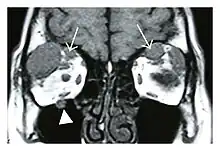

Infraorbital nerve enlargement (IONE) is considered to be a particularly suspicious sign of IgG4-ROD, but seems to occur only when inflammation is in direct contact with the infraorbital canal.[10] IONE is defined as the infraorbital nerve diameter being greater than the optic nerve diameter in the coronal plane.

![]() Bilateral supraorbital nerve enlargements (arrows) and right infraorbital nerve (arrow head) enlargement in a 47-year-old woman with a serum IgG4 of 1000 mg/dL.[1] (T1-weighted MRI) |